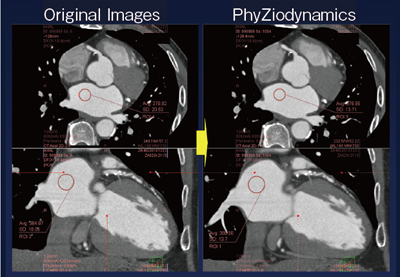

実際の症例について、初期の10症例で検討した結果では、大動脈の内部と心筋について、オリジナル画像とPhyZiodynamicsのSD値を比較したところ、30〜34%の改善が認められた。PhyZiodynamicsの画像では、冠動脈のプラークの辺縁まで明瞭に描出され、ボリューム計測においても壁の部分まで明瞭で詳細な計測が可能で、定量化する場合でも有用である(図2)。

図2 PhyZiodynamicsによる画質の改善